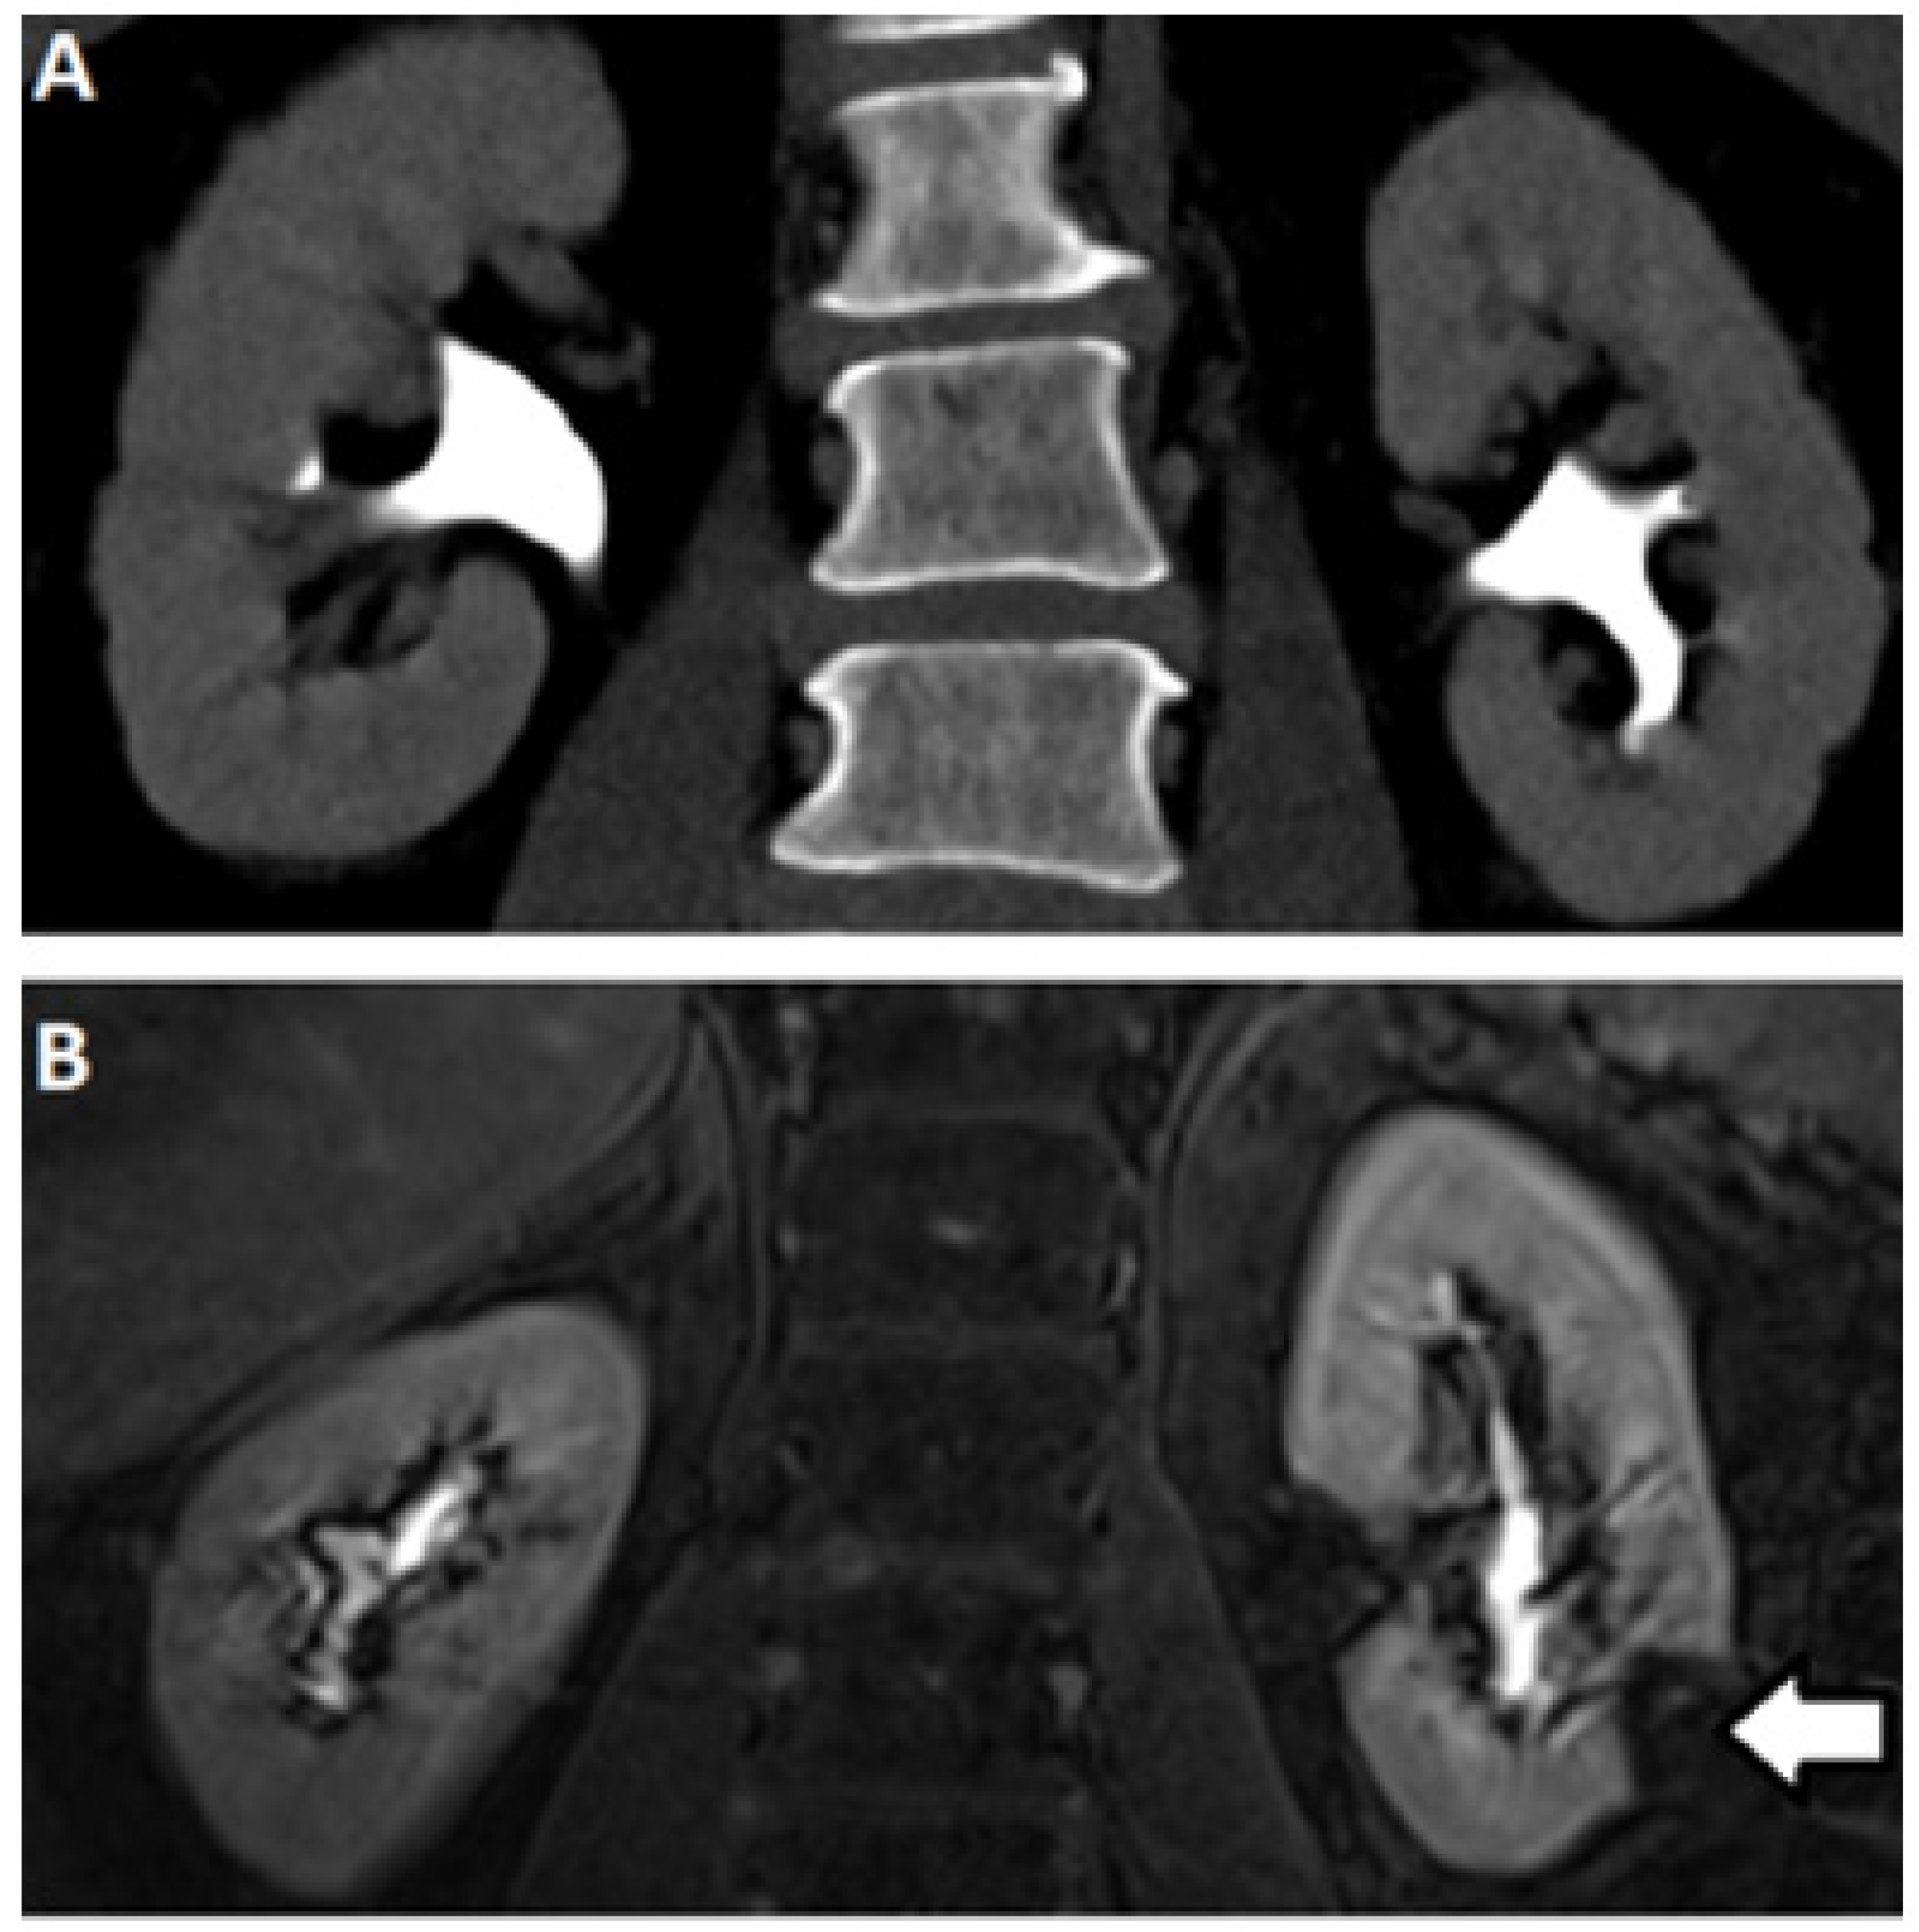

2.3. Computed Tomography

2.5. Magnetic Resonance (MR) Based Urography

3.1. DCE-MR CEST Urography